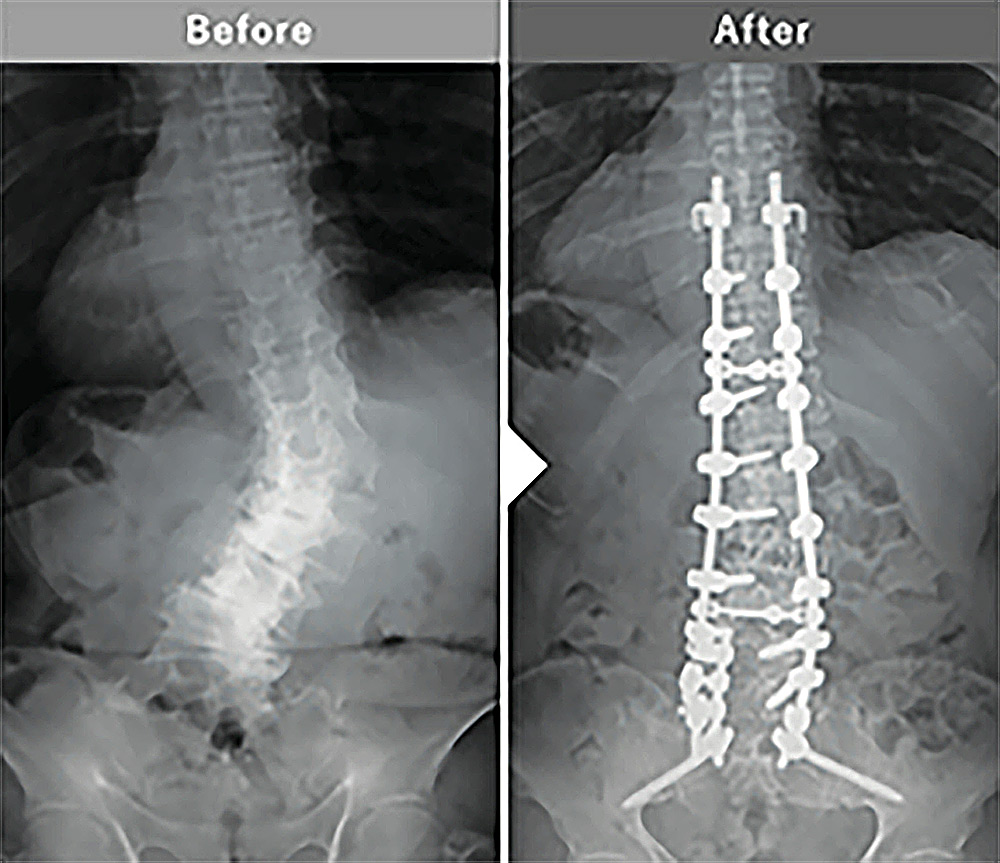

インストゥルメンテーション手術など従来の外科手術と比較して、用いられるスクリューを入れる位置が正確に確認できるようになりました。成人脊柱変形の手術など、スクリューを入れる位置が細く狭い場合などは医師側もかなりの神経を使っていましたが、O-armナビゲーションシステムによって安全に誘導され、成人脊柱変形や側弯症などの矯正固定手術がより安全にできるようになり、患者様の手術後の様子も大きく改善されたと感じます。

矯正固定手術

成人脊柱変形や側弯症に対する広範囲の矯正固定手術